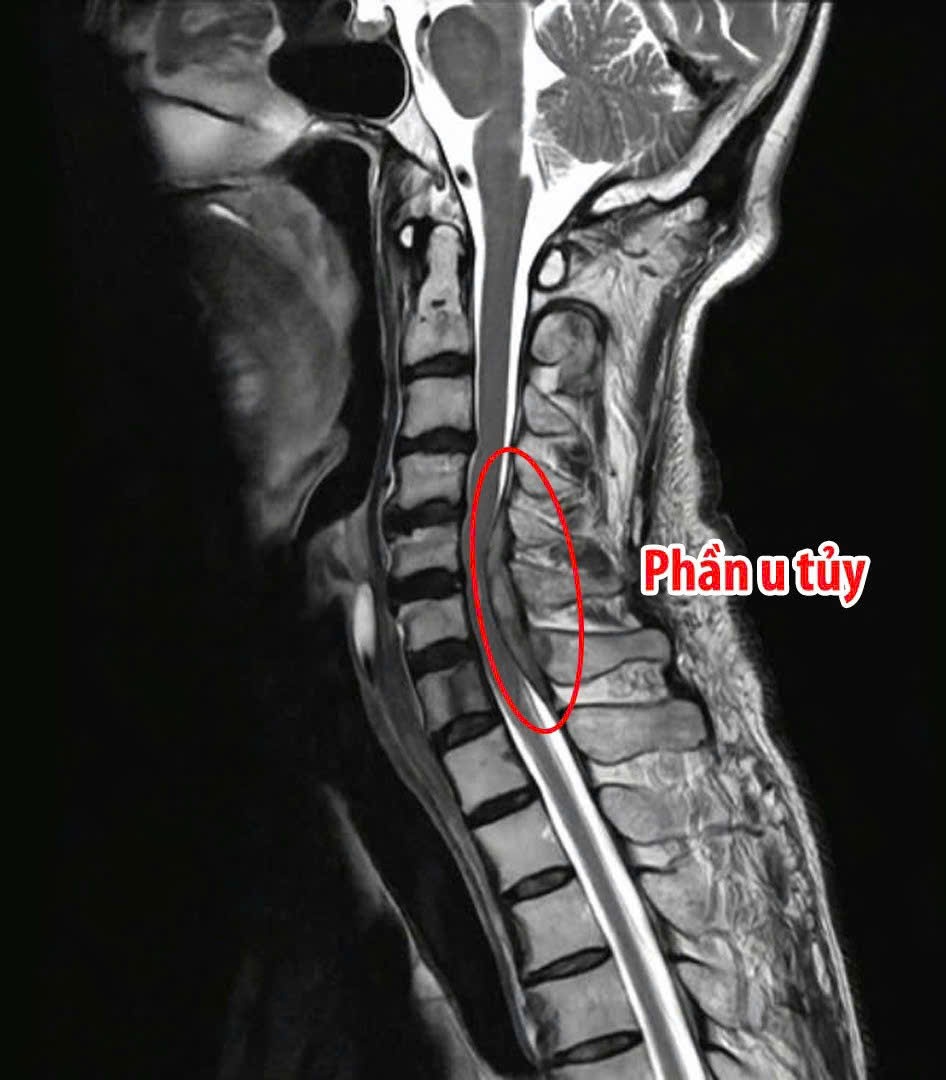

Được biết, bệnh nhân vào BV trong tình trạng yếu liệt cả bốn chi, bí đại tiểu tiện, đau nhiều vùng cổ lan xuống hai tay. Kết quả thăm khám cho thấy sức cơ tứ chi chỉ còn 2/5, gần như mất khả năng vận động. Hình ảnh chụp cộng hưởng từ (MRI) xác định khối u tủy tại đoạn cột sống cổ 5 và 7 gây chèn ép nặng, biến dạng tủy sống kèm phù tủy, một tổn thương nguy hiểm, có nguy cơ dẫn đến liệt. Trước tình trạng nguy kịch của bệnh nhân, ê-kíp y, bác sĩ Ngoại Thần kinh – Cột sống của BV đã tiến hành hội chẩn và quyết định phẫu thuật giải ép tủy, lấy trọn khối u kết hợp cố định cột sống cổ bằng đường mổ sau. Đây là kỹ thuật chuyên sâu, đòi hỏi sự chính xác cao nhằm loại bỏ tổn thương nhưng vẫn bảo tồn tối đa chức năng tủy sống và hệ thần kinh. Sau phẫu thuật, bệnh nhân có nhiều tiến triển tích cực, tình trạng đau, tê hai tay giảm rõ rệt, sức cơ tứ chi phục hồi lên mức 4/5, có thể tự nhấc tay, cử động chân và bước đầu tập vận động trở lại. Hiện nay, người bệnh đang được theo dõi hậu phẫu và kết hợp tập vật lý trị liệu nhằm tối ưu quá trình hồi phục. Mẫu bệnh phẩm cũng đã được gửi làm giải phẫu bệnh để xác định bản chất khối u, phục vụ cho hướng điều trị tiếp theo.